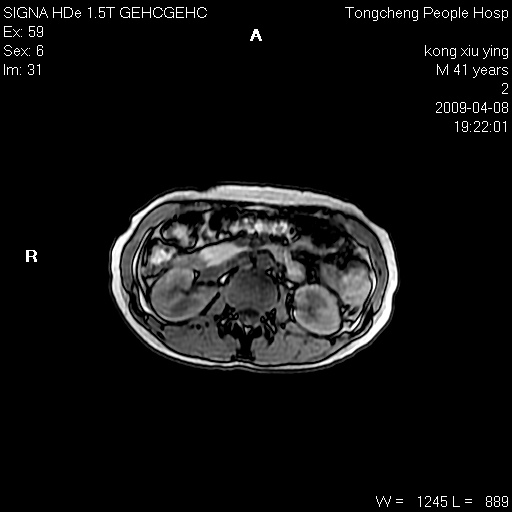

标题: CL1008:【经典】胆囊石榴籽样结石。

女,41岁。健康体检——彩超提示:胆囊显示不清。平素健康,无不适感。

腹部mr扫描及mrcp,图像如下:

胆囊石榴籽样结石。